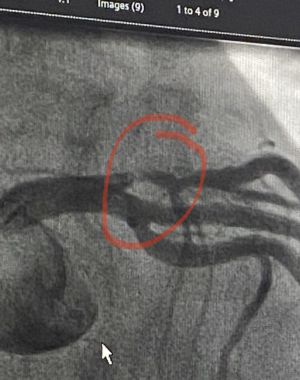

Getting to the heart of the story for women

BY MARY BETH SCHNEIDER

I should have died this past summer. Not the illness kind of death, but the drop-dead kind that makes everyone ask “What happened? She was so fit!” Thankfully, it wasn’t my…